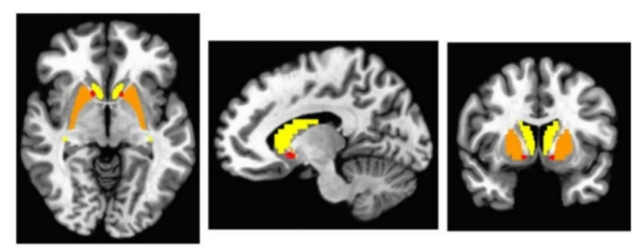

"There has been previous work looking into the total amount of dopamine in the brains of people with autism, but we took a new approach by looking at abnormalities in terms of how dopamine is processed in a specific part of the brain called the basal ganglia via these dopamine transporters," says senior author David Beversdorf, a neurologist from the University of Missouri.

Brain scans on 12 young adults with autism, aged 18-24, revealed abnormal dopamine transporter behavior in two of the 12 participants, with "possible abnormalities" spotted in another two. This means the transporters weren't as uniformly abnormal or asymmetric as expected.